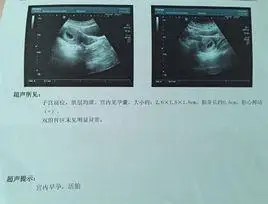

孙茜晒b超照宣布怀孕:谢谢生命的力量(图)